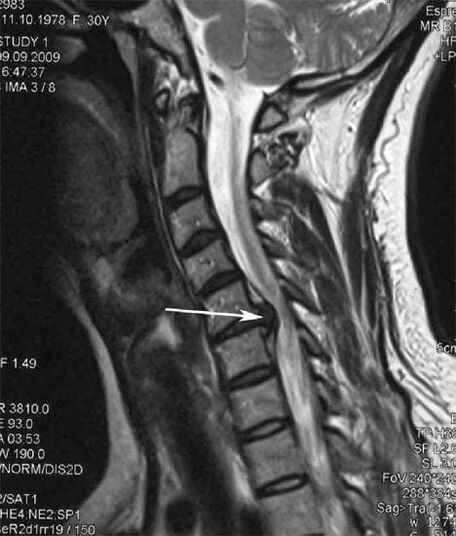

W początkowych stadiach osteochondrozę wykrywa się za pomocą MRI. Później patologię można zdiagnozować za pomocą radiografii. Na radiogramach kręgosłupa szyjnego zauważalne jest zmniejszenie odległości między kręgami, zmiany patologiczne w stawach międzywyrostkowych i osteofitoza.

| Osteochondroza szyjna | Pojawienie się zmian patologicznych w jednym lub kilku segmentach ruchu kręgosłupa. Upośledzona ruchomość kręgosłupa, rozwój zespołów bólowych mięśniowo-powięziowych i ucisk korzeni kręgosłupa | Bóle, parestezje i zaburzenia motoryczne w okolicy szyjnej promieniujące do tyłu głowy i kończyn górnych. Wykrywanie charakterystycznych zmian w kręgosłupie w badaniu rezonansu magnetycznego i radiogramów (osteofity, zmniejszona odległość między kręgami, oznaki uszkodzenia stawów międzykręgowych) |